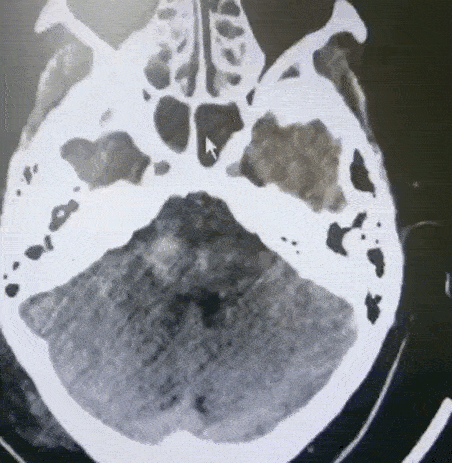

第一次CT 【左】

CT检查提示:中脑基底部和中脑被盖之间,桥脑出血,量约2ml

保守治疗2天后,病情加重,瞳孔进一步扩大,出血量增加